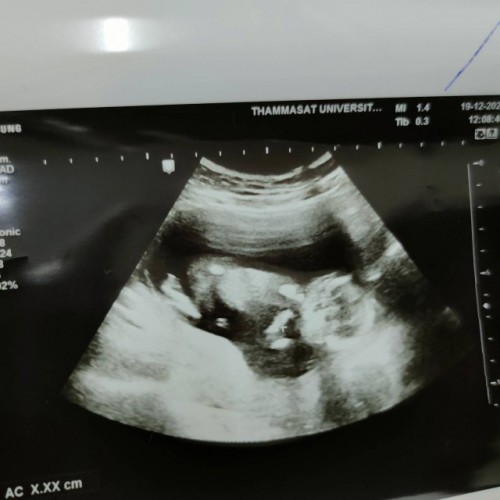

ลูกชายค่ะ นัดผ่า18 พย นี้ 38wค่ะ